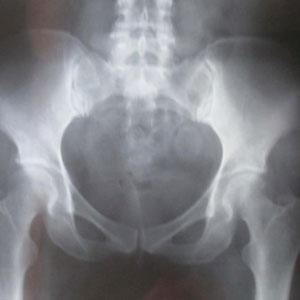

納博特囊腫囊性腫塊,邊界清晰或不清。如囊腫周圍粘連重,則邊界不清;如囊腫與子宮或周圍組織粘連少,則邊界清晰。囊腫多為中等大小,囊腫內可見顆粒狀細小回聲,是囊液粘稠表現。有時因陳舊性血塊濃縮機化而出現較密集的粗光點圖象,呈混合性腫塊狀。腫塊常位於子宮後側,可見囊腫子宮伴隨症。囊腫自發破裂時,聲象圖示後凹陷,囊腫較前縮小。

納博特囊腫超聲圖像示:

(1)本組彩色都卜勒顯示宮區宮旁血流豐富。

(2)本組液性暗區最大直徑18mm,最小直徑5mm,伴有子宮肌瘤7例(占14%),卵巢囊腫5例(占10%),盆腔積液10例(占20%),輸卵管積水2例(占4%),子宮次切術後1例(2%)。

(3)子宮頸肥大18例(占37%)。宮頸厚度在30mm以上,個別達到36mm。部分宮頸回聲可增強。

(4)頸部可見單或多個圓形或橢圓形液性暗區。單發19例(占39%),多發30例(占61%),邊界清晰,後方均伴有增強效應,其中5例還伴有囊壁鈣化。

分析:陰道超聲能彌補婦檢的不足,而且其對檢查者又具有操作簡便、診斷準確、針對性強、無創傷等優點。本組聲像圖具有一般囊腫聲像圖特徵,但其也應與子宮頸肌瘤等相鑑別。在聲像圖上子宮頸肌瘤為低回聲,CDFI示可有包膜血流,無囊腫特有的後壁增強效應。總之,陰道彩超能及時準確地查出已婚婦女的宮頸腺體囊腫,為臨床診斷及治療慢性宮頸炎提供了可靠依據宮頸腺體囊腫為宮頸慢性炎症所致,而臨床醫師僅能觀察到宮頸外口表面的小囊腫,但陰道彩超能查出宮頸深部腺體內所發生的瀦留性囊腫。納氏囊腫本身不引起患者自覺症狀,故未引起患者及臨床醫師的重視。隨著人們生活水平的提高,保健意識的增強;自從超聲診斷儀出現,體檢的婦女逐漸增多。上述49例均為體檢者,其中有宮頸炎的31例,有宮頸肥大18例,大致符合納氏囊腫的病因及病理。